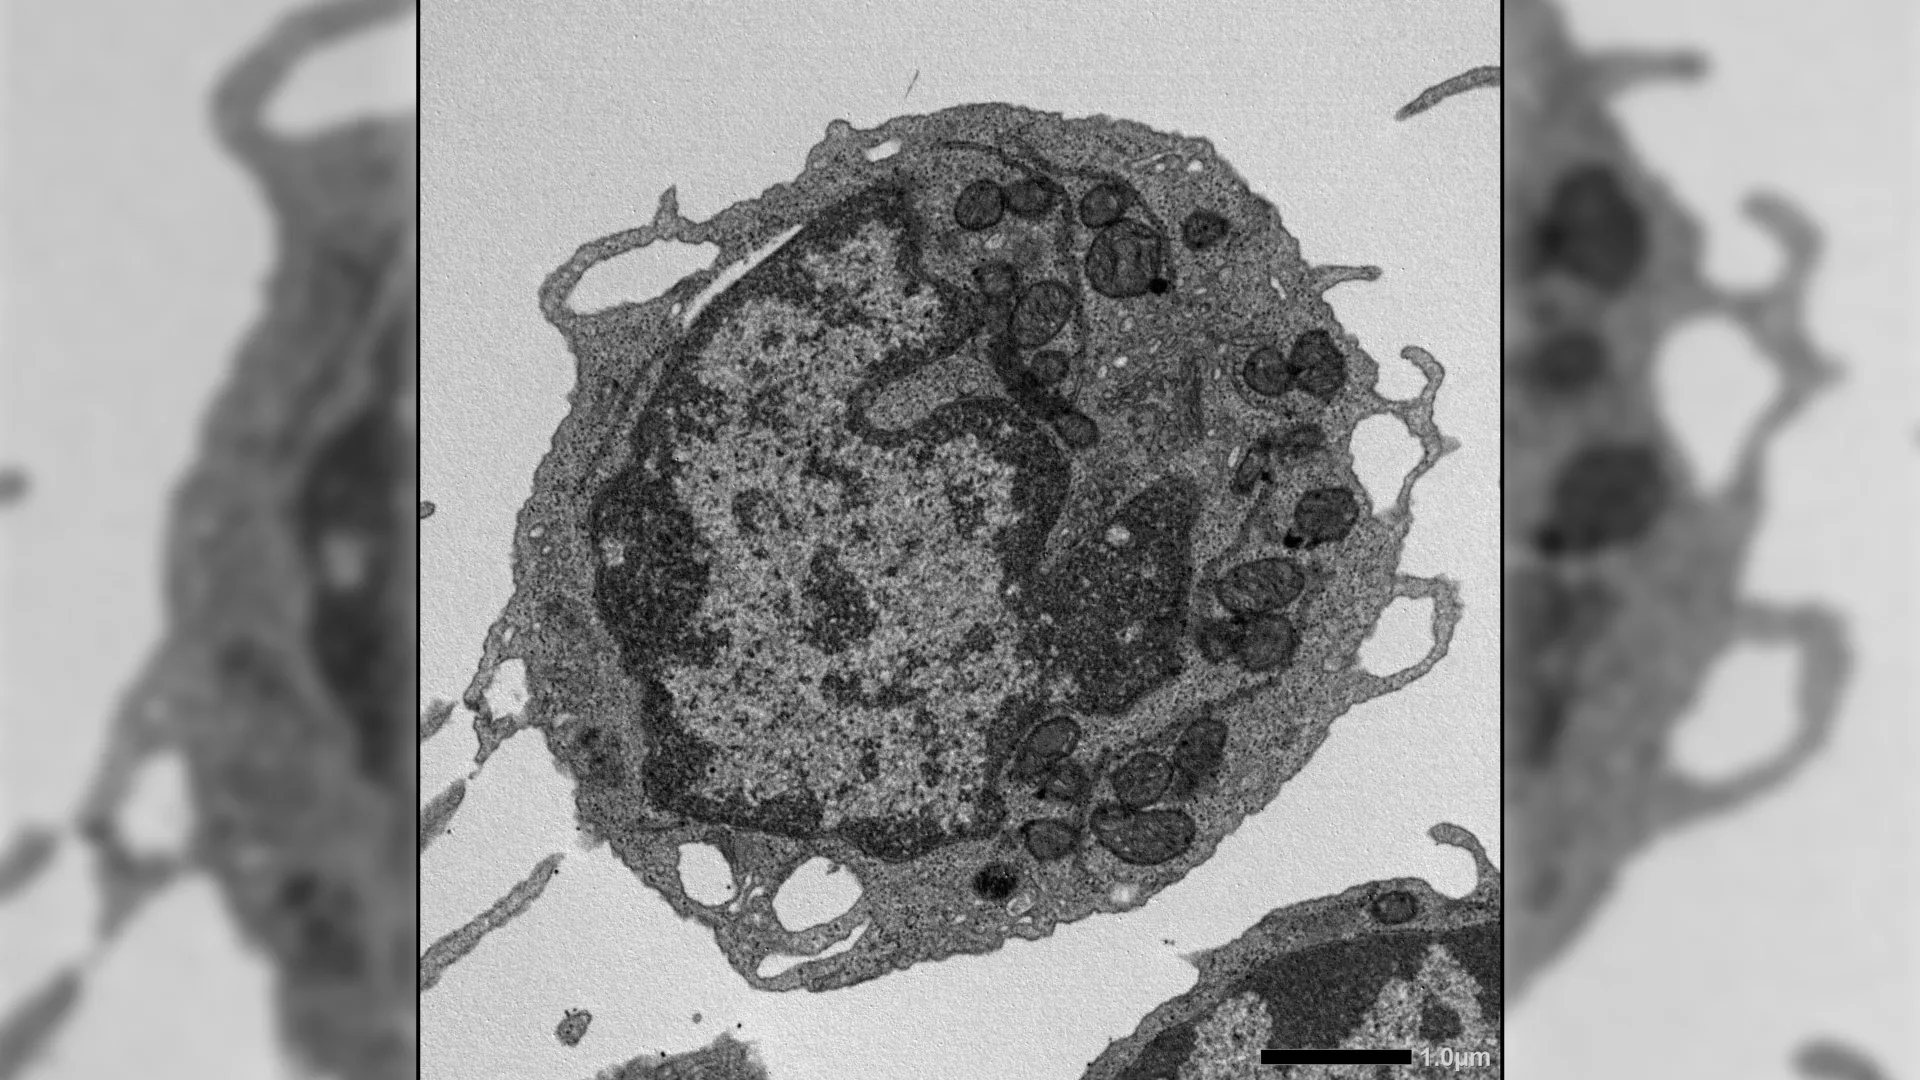

Técnicas adicionais proporcionaram insights mais profundos, incluindo citometria de fluxo, expansão ex vivo, sequenciamento de RNA, ensaio para acessibilidade cromatínica por transposase, imagens de alta resolução, testes metabólicos e estudos detalhados das mitocôndrias. Juntas, essas abordagens permitiram aos pesquisadores examinar como o MLKL afeta as CTHs em múltiplos níveis.

Quando ativado sob estresse, o MLKL se movia brevemente para as mitocôndrias, estruturas que geram energia dentro das células. Ali, causou danos ao diminuir o potencial de membrana, modificar a estrutura mitocondrial e reduzir a produção de energia. Esses efeitos levaram a características-chave do envelhecimento nas CTHs, incluindo uma capacidade reduzida de se renovar, diminuição da produção de células linfoides e uma mudança em direção à produção de células mieloides.